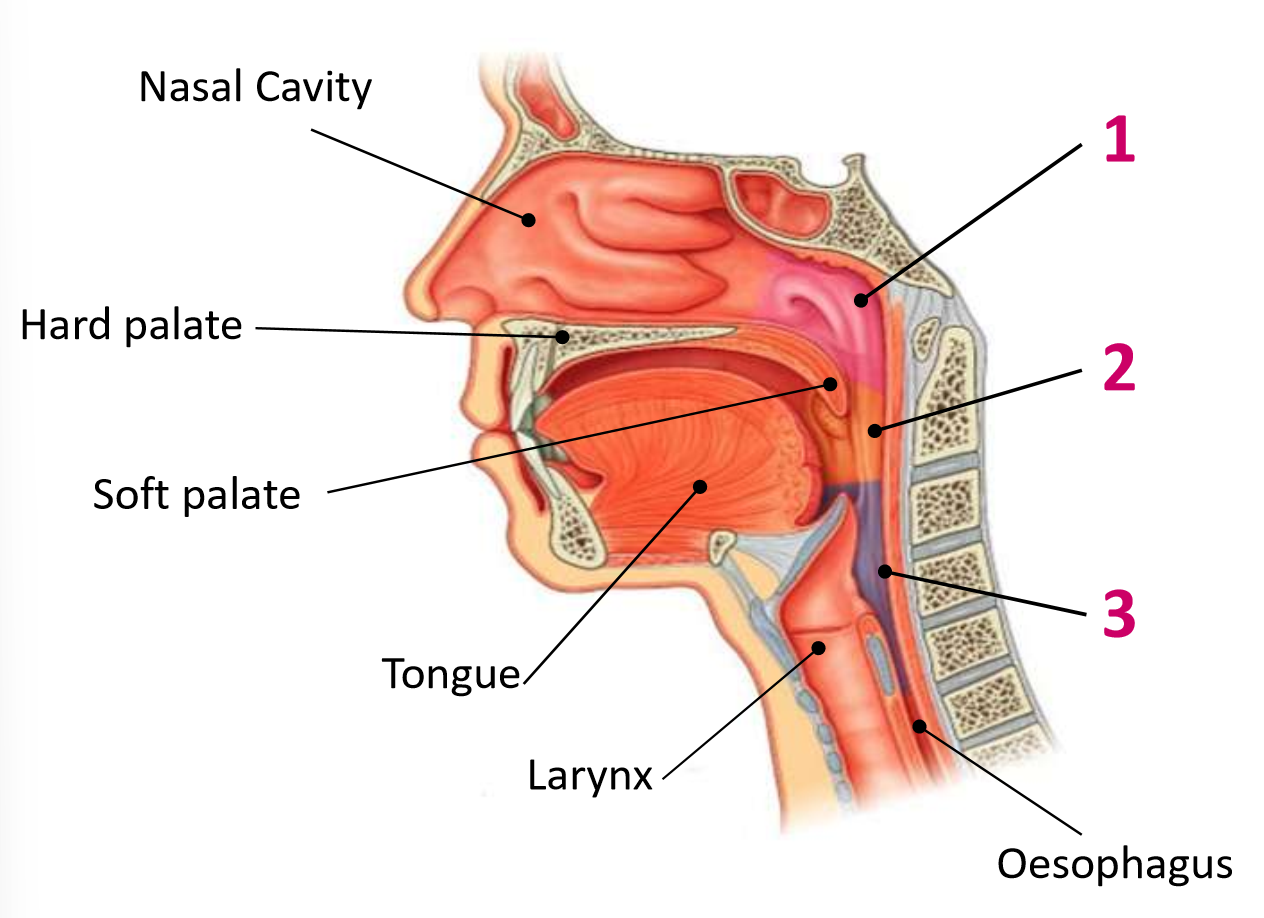

Which area of the head and neck do 1, 2, and 3 make?

pharynx

What region is 1?

nasopharynx

What region is 2?

oropharynx

What region is 3?

laryngopharynx